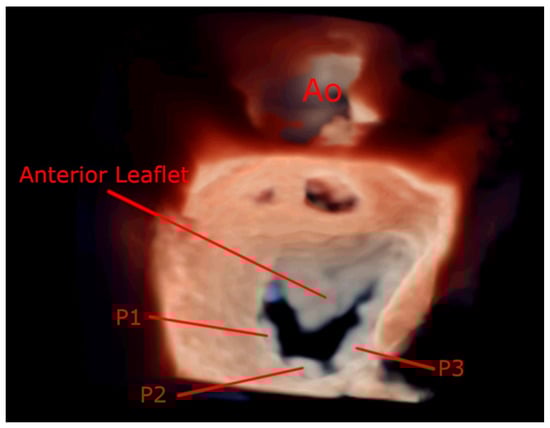

7.4. Focused Wide-Sector (3D Zoom) Imaging

| Anterior Leaflet | Posterior Leaflet | |||||

| Thickness (0–6) (0 = normal, 1 = thickened) | A1 | A2 | A3 | P1 | P2 | P3 |

| Mobility (0–6) (0 = normal, 1 = limited) | 0–1 | 0–1 | 0–1 | 0–1 | 0–1 | 0–1 |

| Calcification (0–10) (0 = no, 1–2 = calcified) | 0–2 | 0–1 | 0–2 | 0–2 | 0–1 | 0–2 |